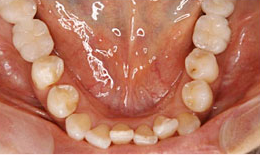

下顎

インプラントを4本埋め込んで、セラミックスクラウンを被せた